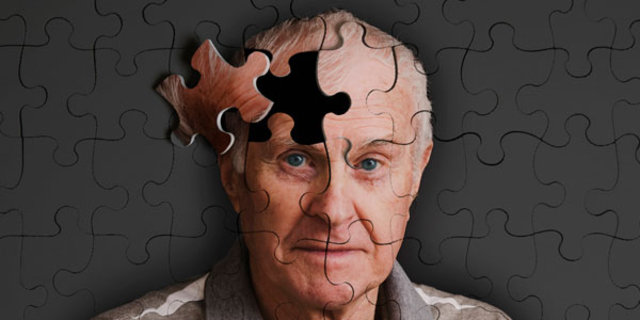

Yaşlılarda ise daha çok; Alzheimer hastalığı, vasküler (damarsal) nedenli unutkanlıklar, Lewy cisimcikli demans (bunama), parkinson hastalığı-demans kompleksi, normal basınçlı hidrosefali gibi nedenler bellek fonksiyonlarında bozukluğa neden olduğu gibi, gençlerde unutkanlığa neden olan faktörler de yaşlılarda hafıza bozukluklarına neden olabileceği unutulmamalıdır.

SİNSİCE İLERLER

Bu her zaman için mümkün olmaz. Bellek bozukluğu bazen sinsi başlar ve erken dönemlerde hasta ve yakınları tarafından kolayca fark edilmeyebilir. Bellek bozukluğunun erken fark edilmesi önemlidir, çünkü bazı bellek bozukluklarının tedavisi mümkündür ve erken tespit edildiğinde tedaviye erken başlanılabilir.

Bellek bozukluğunun erken dönemlerinde önce basit şeyler (isimleri hatırlamada zorlanma, evde ya da işyerinde koyduğu eşyalarını arama gibi ) unutulmaya başlar. Ancak, unutkanlık ve diğer bilişsel fonksiyonlardaki bozulma günlük yaşam aktivitelerini bozmaya başladığında ya da performansı düşmeye başladığında önem kazanır.

UNUTKANLIK CHECK-UP’I

Bellek fonksiyonlarımızın normal olduğunu düşünsek bile unutkanlık check-up yaptırmamızda büyük yarar vardır. Bellek check-up yaptırıldığında, normal bellek performans ölçümü yapılmış olacaktır ve bu da ileride oluşabilecek bellek bozuklukları için referans olacaktır.

Bazen de unutkanlık check-up'ı ile olası bellek bozukluğunun erken safhaları yakalanabilmektedir. Hangi yaşta olursanız olun ve özellikle 50 yaş üstündeki insanların mutlak unutkanlık check-up'ı yaptırmasında büyük fayda vardır. Bilindiği üzere 65-85 yaş arası bunama riski her 5 yılda bir iki katına çıkmaktadır.

Unutmayınız ki, Alzheimer hastalığı gibi nörodejeneratif bunamalarda unutkanlık belirtisi ortaya çıkmadan yaklaşık 10-15 yıl önce beyinde değişiklikler başlamaktadır. Ancak unutkanlık check-up’ı ile erken dönemde silik de olsa bazı bulgulara tespit edilebilmektedir.

Unutkanlık check-up’ı ile kişilerin ruhsal durumu, oriantasyonu, bellek fonksiyonları, anlama, kavrama, algılama, bilgileri öğrenme ve hatırlayabilme fonksiyonları tespit edilebilmektedir.

Bunun yanında kan tetkikleriyle vücutta eksik-bozuk olan ve unutkanlığa yol açan parametreler ortaya konulmakta, beyin görüntüleme (Beyin MRI) ve EEG (Elektroensefalografi) ile de beyinde olabilecek anatomik ve fonksiyonel bozuklukların varlığı ya da yokluğu belirlenebilmektedir.